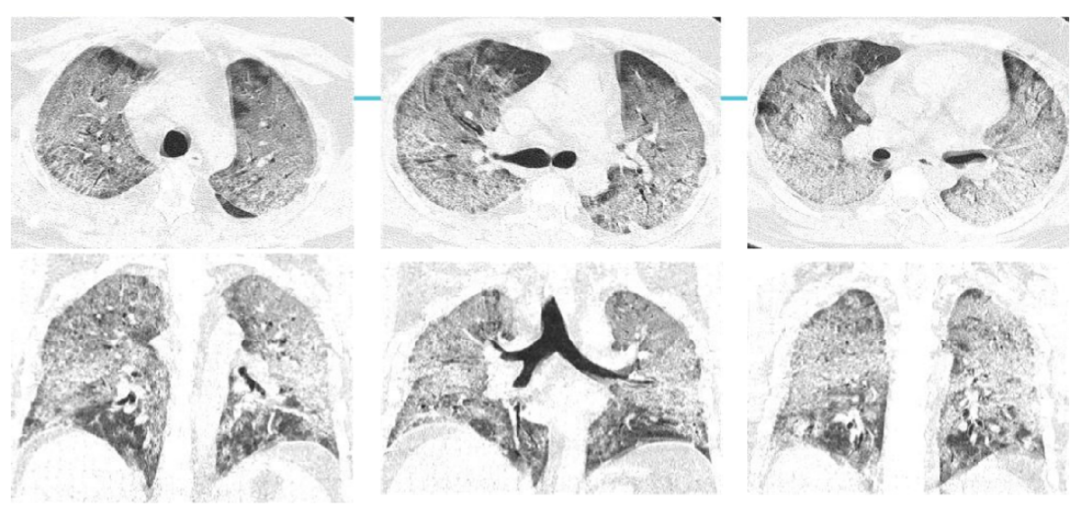

案例三,30歲,男性,確診病例

胸片顯示雙肺彌漫性病變

影像所見:發(fā)熱12天,胸悶、氣喘7天。胸部CT顯示兩肺彌散性磨玻璃影,呈“白肺”改變,其內(nèi)可見空氣支氣管征、雙側(cè)膈面上抬。